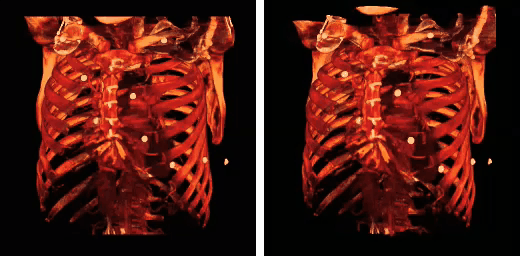

The rib cage is an arrangement of bones in the thorax of all vertebrates except the lamprey and the frog. It is formed by the vertebral column, ribs, and sternum and encloses the heart and lungs. In humans, the rib cage, also known as the thoracic cage, is a bony and cartilaginous structure which surrounds the thoracic cavity and supports the pectoral girdle (shoulder girdle), forming a core portion of the human skeleton. A typical human rib cage consists of 24 ribs, the sternum (with xiphoid process), costal cartilages, and the 12 thoracic vertebrae. Together with the skin and associated fascia and muscles, the rib cage makes up the thoracic wall and provides attachments for the muscles of the neck, thorax, upper abdomen, and back.

Rib fractures are the most common injury to the rib cage. These most frequently affect the middle ribs. When several ribs are injured, this can result in a flail chest which is a life-threatening condition.